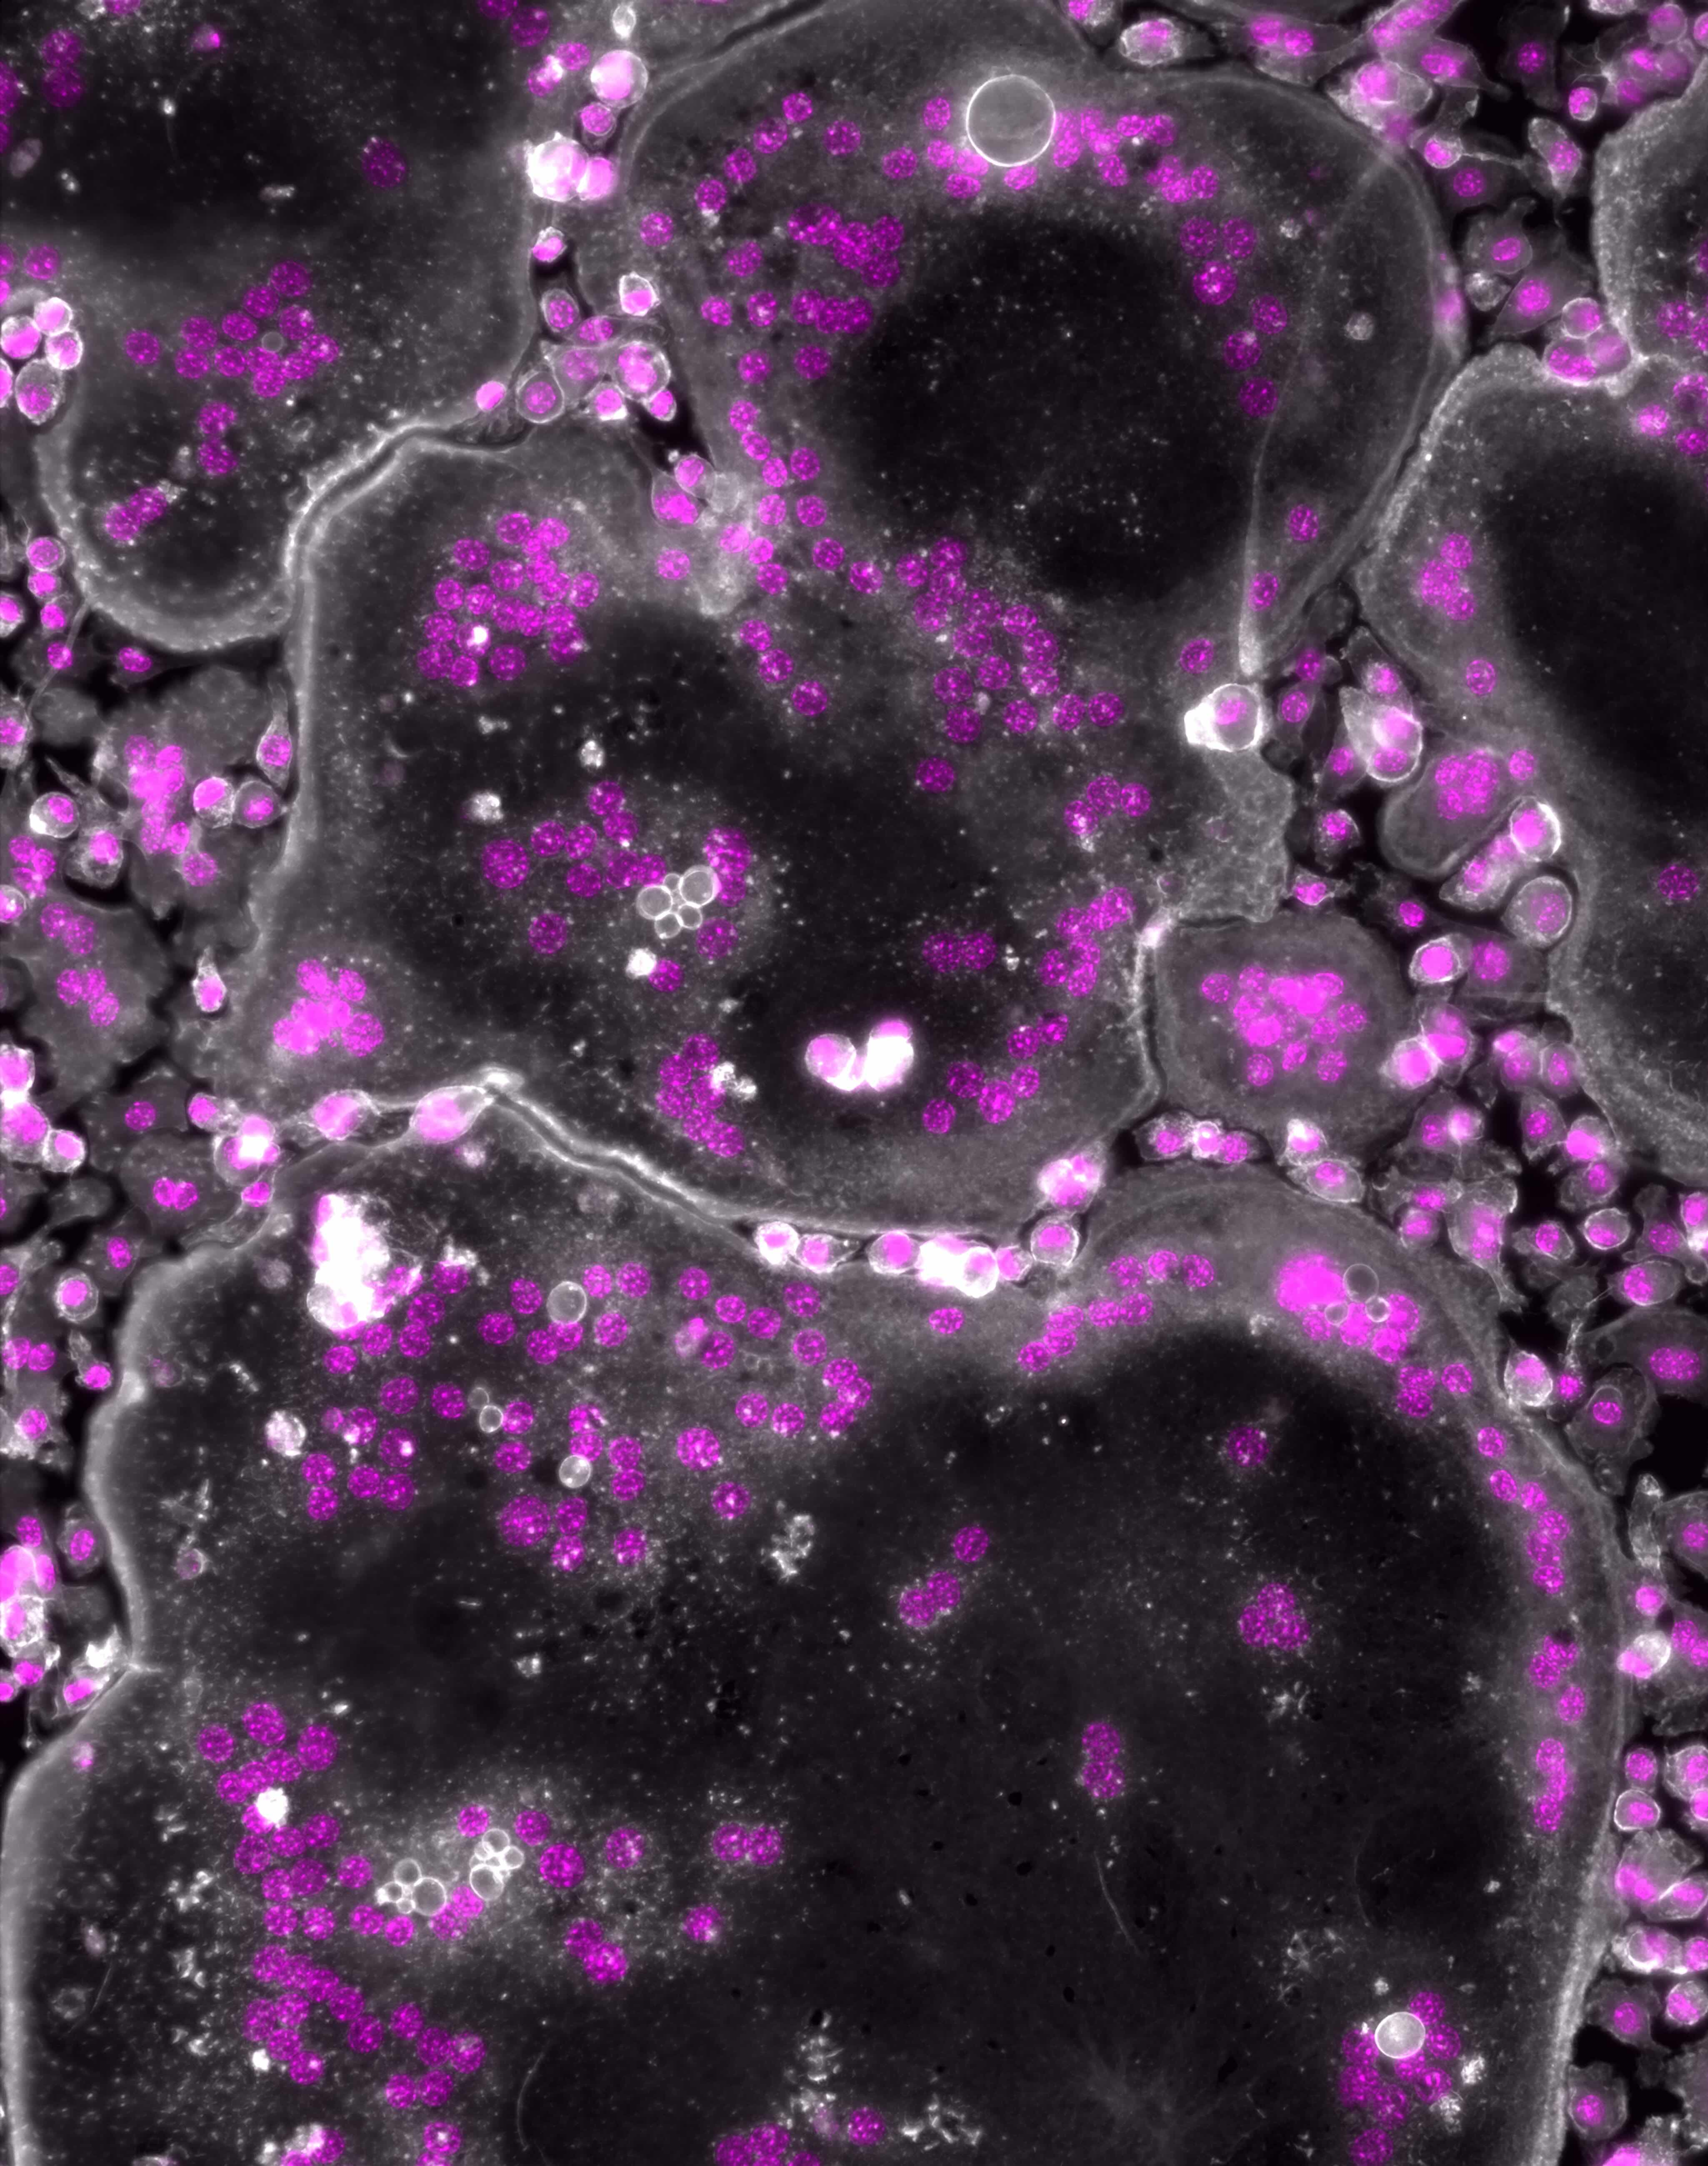

This research provides a deeper understanding of the molecular mechanisms underlying osteoclast function and bone resorption. By identifying moesin as a key regulator of osteoclast fusion, the study opens the door to novel therapeutic strategies for diseases characterized by excessive bone loss, such as osteoporosis and inflammatory bone disorders.

“Our findings highlight cell fusion and moesin as promising targets for modulating osteoclast activity”, said Dr. Vérollet. “By specifically targeting osteoclast-specific regulators of moesin, we may be able to develop treatments that prevent bone loss without disrupting other cellular processes”.